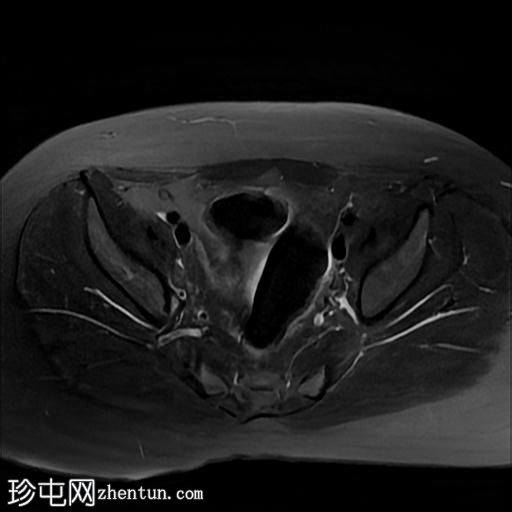

2.jpg

轴位

T2

MRI序列显示:

女性外生殖器

子宫、宫颈及阴道上2/3缺失

左侧睾丸及腹股沟管内环

右侧睾丸位于腹腔内,靠近腰大肌

双侧卵巢未显影

MRI结果提示雄激素不敏感综合征 (AIS),患者基因构成为男性,但外生殖器为女性(46XY核型)。由于细胞对睾酮等雄激素产生抵抗,雄激素不敏感综合征常伴有双侧隐睾。